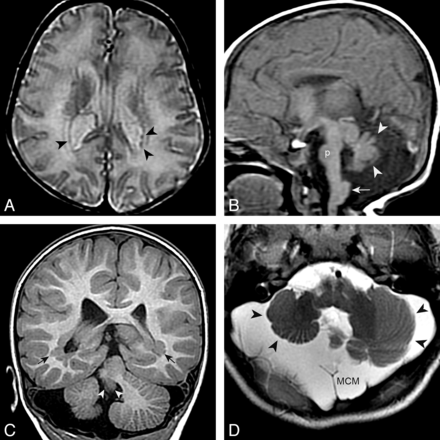

Abnormalities were common in the brain stem (19.5%), cerebellar vermis (28%), and cerebellar hemispheres (15%; On-line Table 6). Malformations of the brain stem (31.0% versus 9.3%, P < .014) and vermis (37.9% versus 14.0%, P = .007) were more strongly associated with pPNH than aPNH, respectively (Fig 4). Cerebellar hemispheric malformations were associated more strongly with many PNHs (group 3, 21.4%) than fewer (groups 1 and 2, 16.2%, P < .017) and with pPNH (24.1%) rather than with aPNH (7.0%, P < .031). The overall frequency of megacisterna magna in patients with PNH was 12% (On-Line Table 6); megacisterna magna was more strongly associated with dPNH (31.3%) than with aPNH (0.0%, P < .0001) or pPNH (5.2%, P = .0013) and with >10 PNH (21.4%) than with <10 PNH (6.7%, P < .0001).

pPNH and posterior fossa anomalies. A and B, An 11-day-old boy with microcephaly. Small PNH are present in the trigones (black arrowheads in A [axial T2 spin-echo–weighted image]). Other findings include a small pons (p in B [sagittal T1 spin-echo–weighted image]), a hypoplastic and dysmorphic vermis (white arrowheads), and a large inferior cerebellar peduncle (arrow). C and D, A 2-year-old boy with PNH in the trigones (black arrows in C [coronal T1 inversion recovery–weighted image]) and a very small vermis (white arrowheads), dysplastic and small cerebellar hemispheres (black arrowheads), and megacisterna magna (MCM).